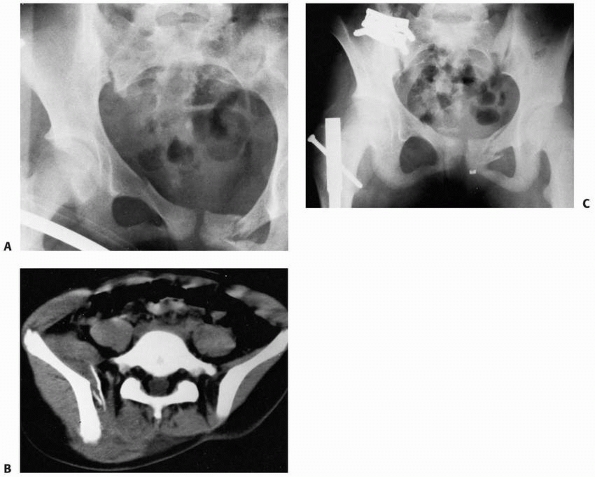

![]() |

FIGURE 20-18 A.

Multiple trauma in this 12-year-old child included three fractures of the pubic rami, disruption and fracture of the sacroiliac joint on the right, and a femoral shaft fracture on the right. B. CT shows fracture of the ilium and disruption of the sacroiliac joint. C. After open reduction and internal fixation of the sacroiliac joint and closed intramedullary nailing of the femoral shaft fracture. Note femoral nail inserted through the tip of the greater trochanter. |